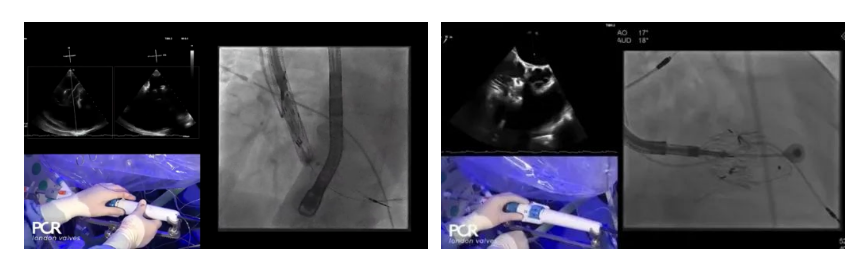

手術在全麻狀態(tài)下開展,采用經右側頸靜脈入路的方式將輸送器送入患者心臟內,在TEE及DSA引導下調整輸送器頭端角度,使得輸送器與三尖瓣瓣環(huán)平面垂直。在輸送器進入右心室后釋放室間隔錨定裝置,而后釋放瓣葉夾持件(2個耳片結構)成垂直狀態(tài)。在TEE及DSA確定夾持件固定至三尖瓣葉根部且位于右室側后釋放人工瓣心房側盤片。隨后調整瓣膜同軸性以及室間隔錨定件位置(貼合室間隔),前推藏針管并固定,進而釋放室間隔錨定裝置,并再次確認瓣膜位置、穩(wěn)定性及同軸性,合攏輸送鞘后撤出輸送器,完成LuX-Valve Plus人工三尖瓣瓣膜的植入。